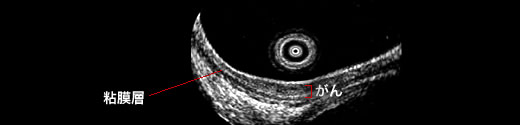

(5) 超音波内視鏡検査

図4. 超音波内視鏡による食道粘膜癌の診断

食道壁の各層の描出が可能で、粘膜にとどまる癌がわかります。

内視鏡の先端につけた超音波装置によって、食道内腔から癌の深さを精密に評価します。内視鏡的粘膜切除で切除可能な癌の診断に不可欠です。また、食道の外側にあるリンパ節の診断にも有用です 。